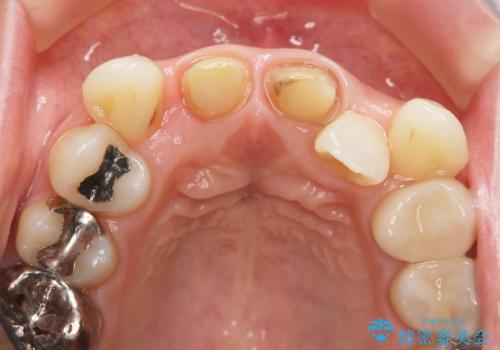

X線写真より不十分な根管治療、根尖病変、前歯の変色が認められます。

歯根の近接のみられる右上側切歯を抜去し、根管治療を伴うセラミック治療を計画します。

歯根近接について

叢生が著しく、歯根の近接が見られる場合歯磨きができず歯石がたまりやすく骨吸収の原因となることが多いです。

このような場合矯正や転位歯の抜去が治療方法として挙げられます。